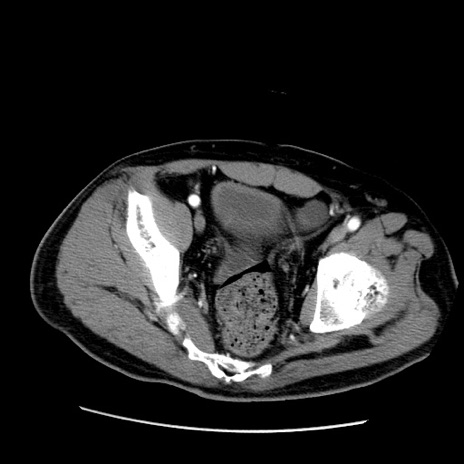

症例22(横断像)

【症例】50歳代男性

【主訴】腹痛

【現病歴】AVMからの被殻出血のため回復期リハ病棟入院中。 本日午後3時頃急に下腹部痛が出現した。

【既往歴】AVM、被殻出血、虫垂炎、高血圧

【身体所見】意識晴明、左半身不全麻痺、会話の理解は良好、36.5°C、腹部:膨隆、全体に板状硬、下腹部正中に圧痛点あり、反跳痛-、筋性防御不明、右下腹部にope scar

【データ】WBC 9400、CRP 0.06